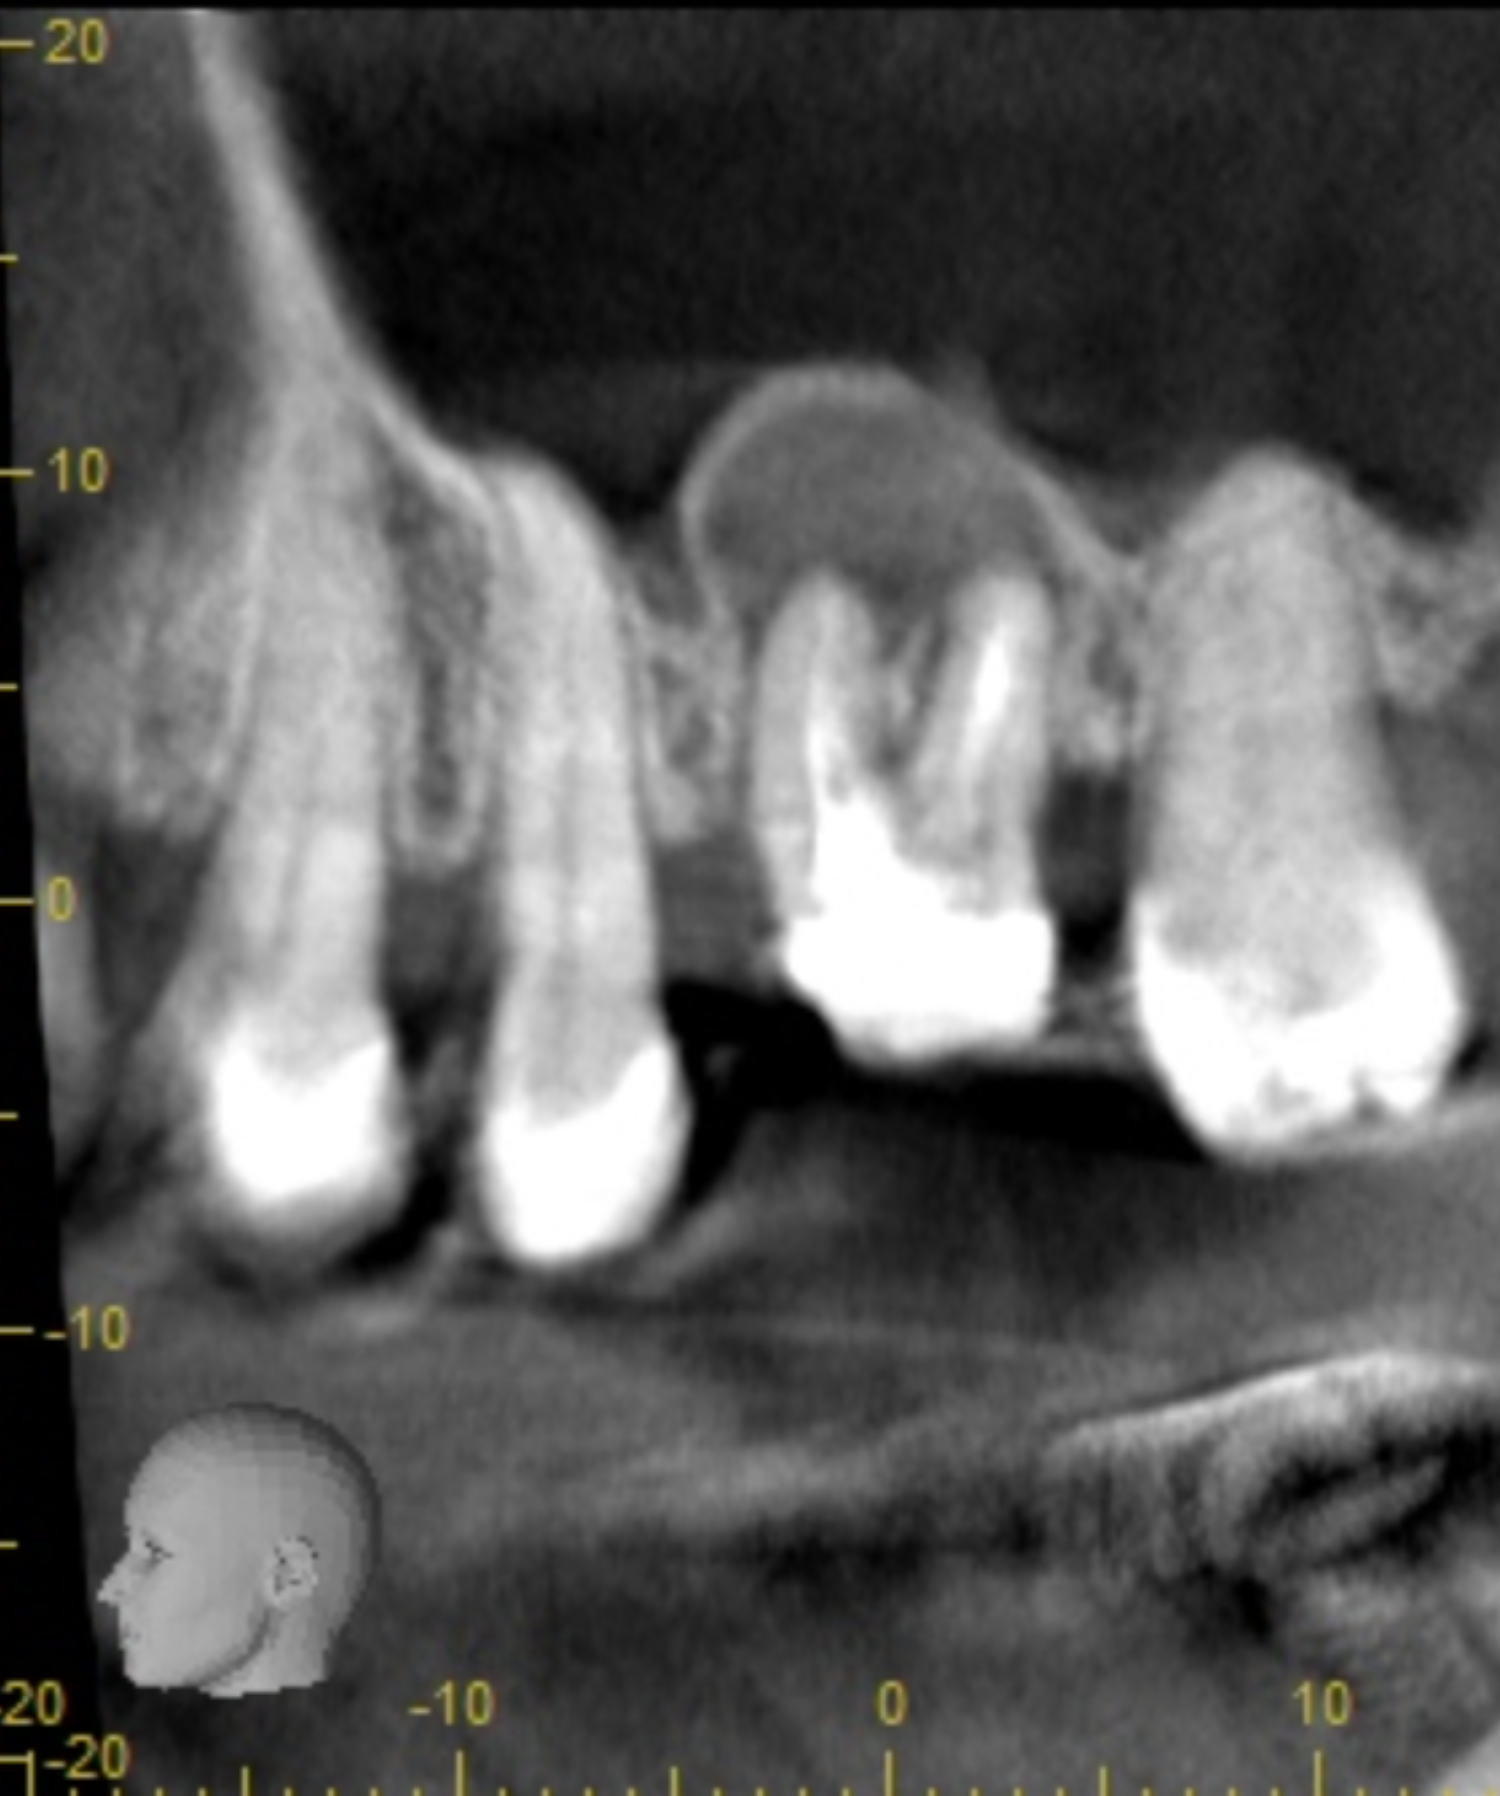

KK2227様

| 通院時年齢 | 55 | ||||||||||

|---|---|---|---|---|---|---|---|---|---|---|---|

| 性別 | 男性 | ||||||||||

| 通院目的 | 右上の歯が取れた | ||||||||||

| 診断 | ①右上7根尖性歯周炎 ②重度う蝕 ③左上7歯髄に近接するステージ3のう蝕 |

||||||||||

| 処置内容 (または主訴) | ①マイクロスコープによる根管治療 ②マイクロスコープによるう蝕除去およびセラミック修復 ③MTAを用いたマイクロスコープによる歯髄温存療法からセレック修復 |

| 通院期間 | 半年 | ||||||||||